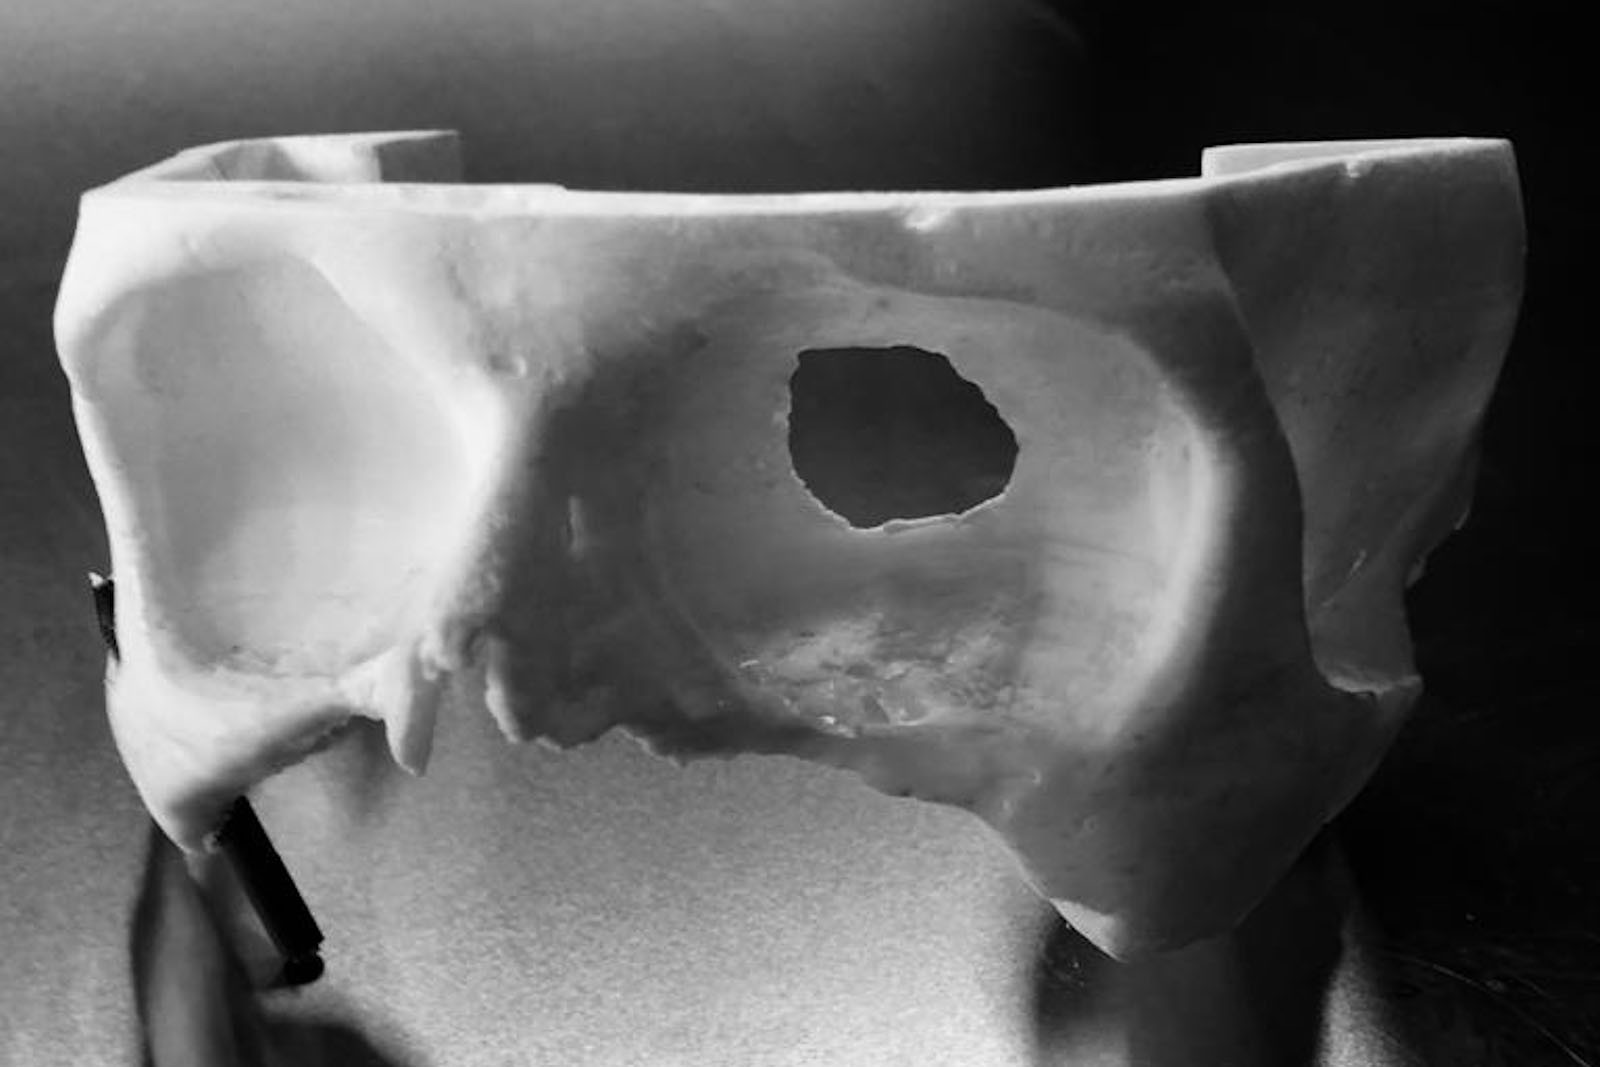

Chory po resekcji tkanek/narządów twarzoczaszki wymaga wnikliwej diagnostyki obrazującej zakres ubytku oraz stan podłoża kostnego. Wykonuje się zdjęcia radiologiczne RTG pantomograficzne szczęk OPG, konwencjonalną tomografię komputerową CT, stożkową tomografię komputerową CBCT, ukazującą trójwymiarowy obraz twarzoczaszki, oraz w razie potrzeby rezonans magnetyczny NMR. Możliwy jest również druk modeli 3D w skali 1:1 dowolnej części twarzoczaszki.

Diagnostyka ma za zadanie wykluczenie wznowy wyciętego nowotworu oraz pomoc w ocenie tkanki kostnej w okolicy ubytku. Ocena kości pozwala na zaplanowanie zabiegu wszczepienia implantów jako przyszłego fundamentu niezbędnego dla mocowania protez poresekcyjnych lub epitez twarzy.

Zastosowanie współczesnych technik obrazowania trójwymiarowego umożliwia precyzyjne zaplanowanie pozycji implantów czaszkowych, tak by ektoprotezę stabilnie osadzić na podłożu.